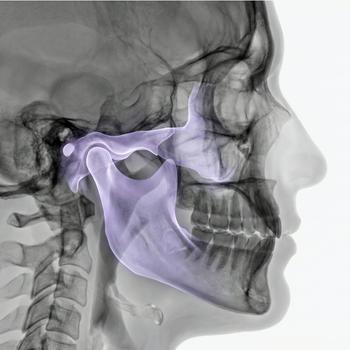

Preparations for an MRI scan

The scan cannot be performed if you have a pacemaker, insulin pump, metal splinter or other implanted electronic equipment. Implants such as hip prostheses or dental fillings are usually not an obstacle.

Book an MRI of the pelvis – get a referral immediately

An MRI of the pelvis helps you and your doctor understand the cause of your symptoms and choose the right treatment. The scan takes approximately 30–45 minutes, is completely painless and does not require any special preparation. We issue a referral in connection with your order, and you will receive a written opinion from a specialist within a few days.